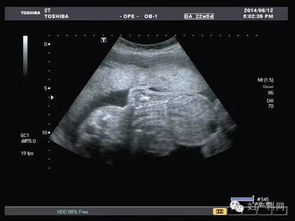

在懷孕第34周第二次超聲波檢查的目的是監(jiān)測(cè)羊水量、胎盤(pán)位置、胎盤(pán)成熟度及胎兒有無(wú)畸形,了解胎兒發(fā)育與孕周是否相符。 最后是在第37周以后,超聲檢查主要目的是確定生產(chǎn)方式,為了監(jiān)測(cè)羊水量、胎盤(pán)成熟度,必要時(shí)需要每周一次B超。

當(dāng)然這只是最常規(guī)的檢查,如果孕婦在懷孕早期出現(xiàn)陰道出血、突然腹痛等情況,可以借助B超確定胎兒是否存活、有無(wú)異常妊娠。其次,如果孕婦患有糖尿病、高血壓等其他影響妊娠的疾病,都要增加超聲檢查的次數(shù)。